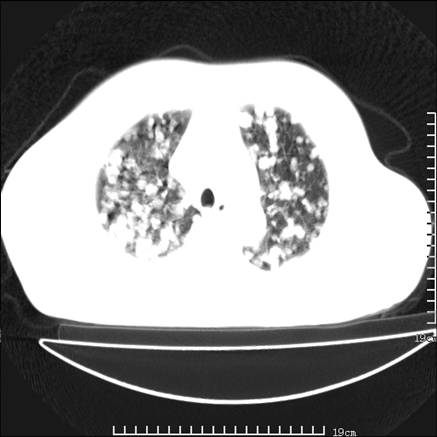

张男,75岁,干咳半年余,小便不利二年,b超检查前列腺增大,未见明显肿块;前列腺癌血生化检查多项指标明显增高。

双肺内多发转移瘤,纵膈淋巴结转移。来源前列腺?建议盆腔mri进一步检查。

双肺转移满了。

两肺广泛转移瘤。